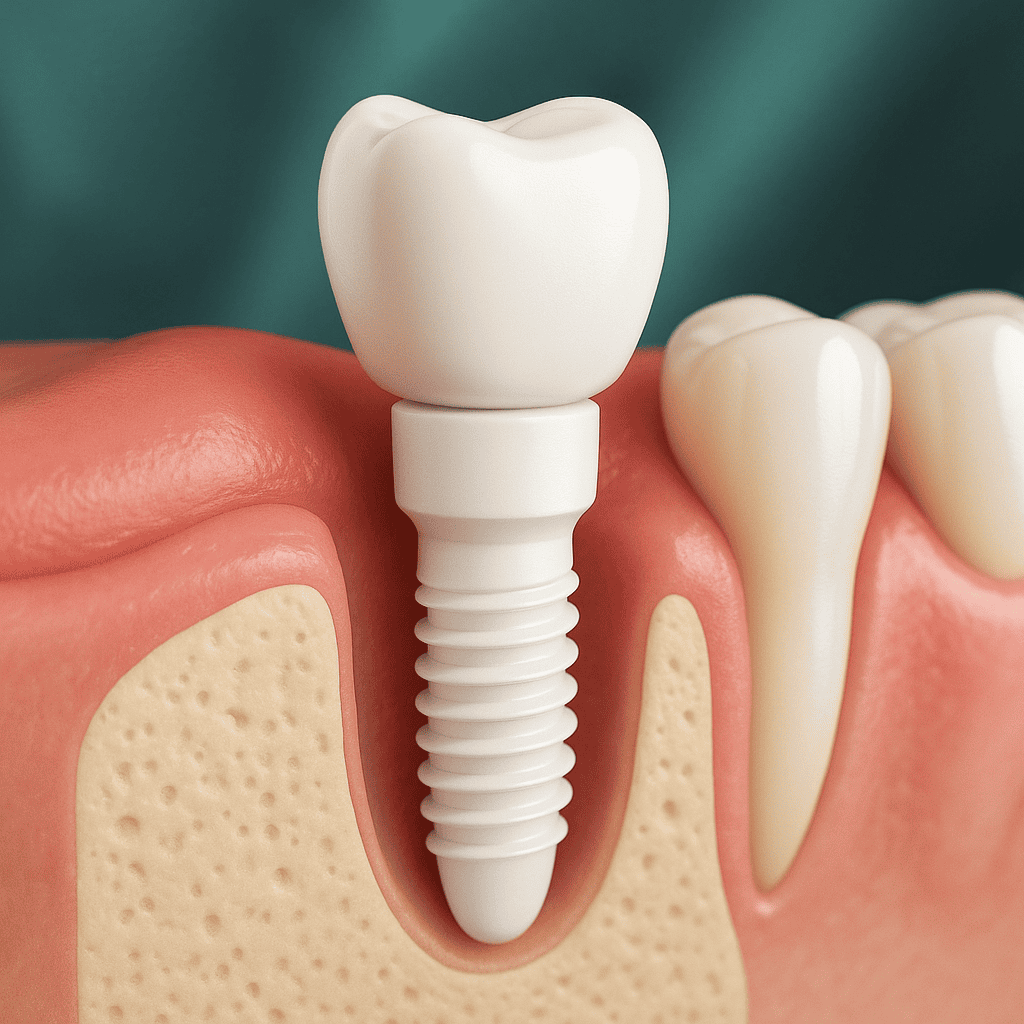

Qual è la differenza tra impianti in titanio e impianti in zirconia?

Impianti in zirconia (zirconio): la zirconia è un materiale ceramico bianco, privo di metallo, apprezzato per l’eccellente estetica e l’alta biocompatibilità. È particolarmente indicata per pazienti allergici ai metalli o per chi desidera un risultato completamente bianco, senza il tipico alone grigiastro a livello gengivale. Gli impianti in zirconia possono essere in uno o due pezzi e richiedono un posizionamento molto preciso per garantire risultati affidabili e naturali.

Quale impianto scegliere? Il titanio resta lo standard di riferimento, soprattutto nei casi complessi o per le riabilitazioni posteriori. La zirconia è invece preferita per motivi estetici e nelle zone visibili. In Turchia, la scelta viene sempre definita dopo una valutazione clinica completa.

Inserimento dell’impianto

In anestesia locale, l’impianto viene inserito nell’osso mascellare. Se necessario, può essere eseguito un innesto osseo. La procedura dura generalmente tra 30 minuti e 1 ora per impianto.

È previsto un periodo di 3–6 mesi affinché l’impianto si integri perfettamente con l’osso. Nel frattempo può essere posizionata una protesi provvisoria in attesa della corona definitiva.

Posizionamento della corona definitiva

Una volta completata l’integrazione, viene fissata una corona in ceramica o in zirconia, progettata per armonizzarsi con i denti vicini e garantire una masticazione confortevole e naturale.